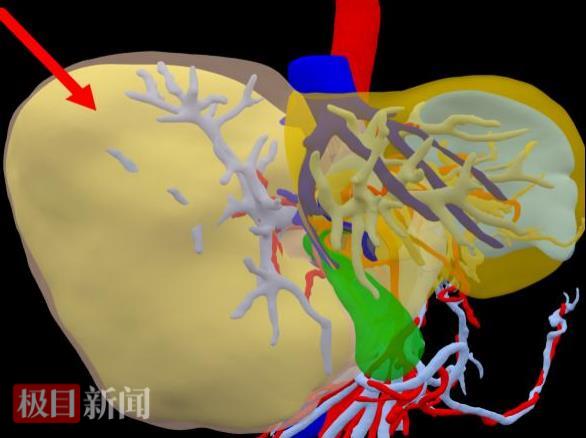

三维重建图,红色箭头示肿瘤(前面观)

通过三维重建分析,切除肿瘤及部分周边肝组织后,剩余肝的体积约占标准肝体积的50%,符合安全手术切除的条件。在充分的术前准备后,胡少勃团队为黄先生进行了手术。